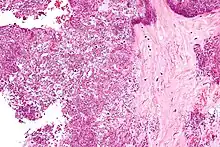

The disease is defined by presence of joint inflammation and the presence of CPPD crystals within the joint. The crystals are usually detected by imaging and/or joint fluid analysis.

Arthrocentesis, or removing synovial fluid from the affected joint, is performed to test the synovial fluid for the calcium pyrophosphate crystals that are present in CPPD. When stained with H&E stain, calcium pyrophosphate crystals appears deeply blue ("basophilic").[10][11] However, CPP crystals are much better known for their rhomboid shape and weak positive birefringence on polarized light microscopy, and this method remains the most reliable method of identifying the crystals under the microscope.[12] However, even this method has poor sensitivity, specificity, and inter-operator agreement.[12]

These two modalities currently define CPPD disease, but lack diagnostic accuracy.[13] Thus, the diagnosis of CPPD disease is potentially epiphenomenological.